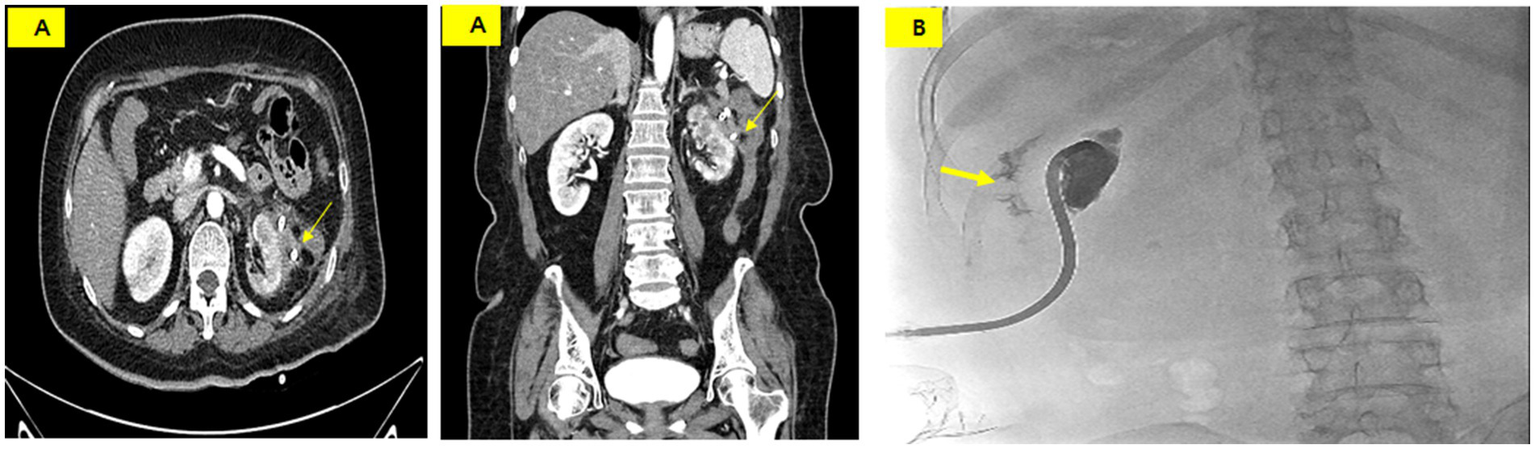

An ileostomy was performed to prevent fecal material from passing into the perinephric abscess on the 26th day of hospitalization. Draining of the fluid culture at this time revealed complicating pathogens, including Klebsiella pneumoniae, Enterococcus faecium, Candida albicans, and Candida glabrata. Vancomycin, ceftriaxone, and micafungin were administered intravenously. On the 30th day of hospitalization, the PCD catheter was removed as the infection spread from the abscess to the skin along the catheter tract. The PCD catheter was then reinserted at another site. Subsequently, tube repositioning was performed once every 7 days to maintain the drainage volume. A CECT performed on the 60th day of hospitalization showed that the abscess had nearly disappeared (Figure 4A). A tubogram via the PCD catheter showed contrast leakage into the descending colon but nearly complete disappearance of the previous prominent fistula tract (Figure 4B).

Figure 4

(A) CT scan on hospital day 60 showing a marked reduction of the abscess and a suspicious fistula or adhesion between the perinephric abscess and the descending colon (thin arrow). (B) Tubogram showing residual contrast leakage into the colon (thick arrow) but near resolution of the fistula tract.